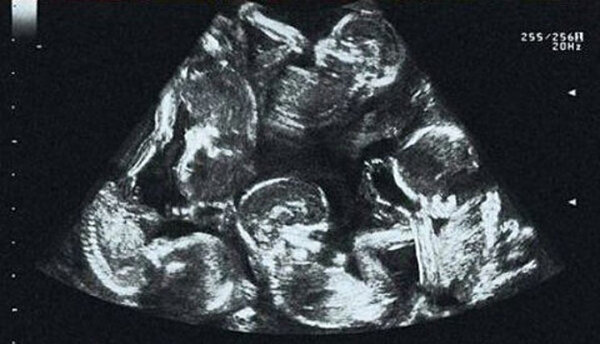

Dívka prošla všemi plánovanými prohlídkami. A nějak, na jedné z těchto prohlídek se odhalilo zcela nečekané! Lékaři již počítali pět dětí. Dívka se nemohla ovládnout a propukla v slzy. Vůbec ne ze strachu, ale spíše ze štěstí. Koneckonců, ne každou ženu si vesmír vybere pro takovou misi - paterčata se rodí pouze jednou za několik století.

Na nadcházející setkání s dětmi se velmi pečlivě připravovali nejen budoucí rodiče a celý personál nemocnice. Lékaři z jiných měst České republiky přijeli speciálně do nemocnice, aby sledovali narození tohoto zázraku.